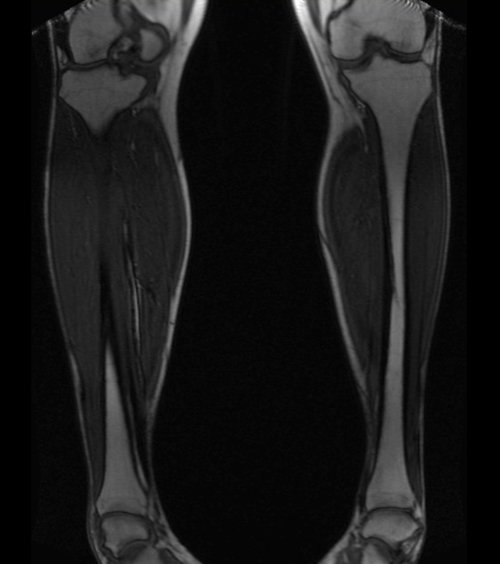

LOWER LEG